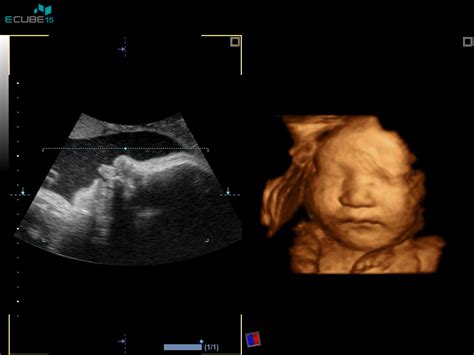

Spremljanje rasti v nosečnosti

Spremljanje rasti ploda v nosečnosti je prav tako ključno. V Sloveniji se je po osamosvojitvi zakonodaja glede spremljanja nosečnosti spremenila, kar je nekatere nosečnice pustilo brez rutinskega tretjega kontrolnega ultrazvoka. Trenutno se rast ploda pogosto spremlja s centimetrskim trakom za merjenje razdalje med sramno kostjo in vrhom maternice. Če se izkažejo nepravilnosti pri rasti, je smiselno preveriti tudi pretoke v popkovnični arteriji, srednji možganski arteriji in v materničnih arterijah. Rast ploda običajno preverjamo na 14 do 21 dni, optimalno pa je, da preglede opravlja isti preiskovalec na istem UZ aparatu za večjo natančnost.